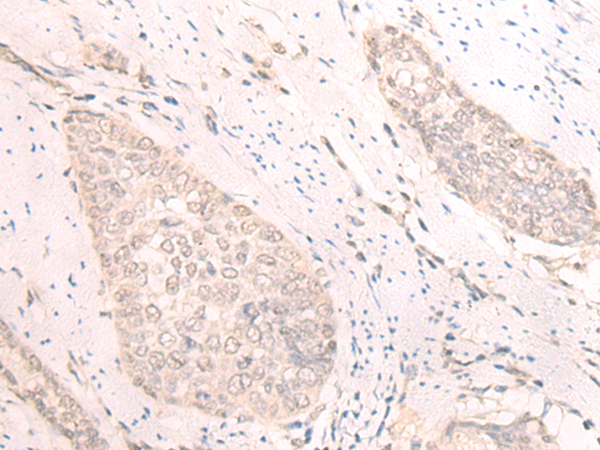

Product Image

The image is immunohistochemistry of paraffin-embedded Human thyroid cancer tissue using (TBC1D2 Antibody) at dilution 1/25. (Original magnification: ×200)

The image is immunohistochemistry of paraffin-embedded Human esophagus cancer tissue using (TBC1D2 Antibody) at dilution 1/25. (Original magnification: ×200)